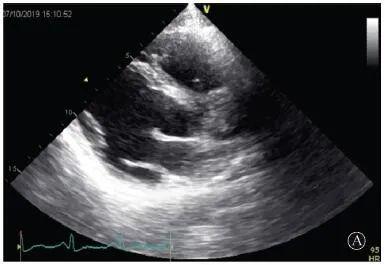

患者入院后無特殊不適,心率70次/min,血壓110/60 mmHg,心功能Ⅱ級。查血常規(guī):血紅蛋白139 g/L,白細胞7.39×109/L,血小板221×109/L。尿常規(guī)、便常規(guī)+潛血均正常。生化:丙氨酸氨基轉移酶38 U/L,白蛋白47 g/L,鉀3.9 mmol/L,肌酐(酶法)65 μmol/L,總膽固醇3.52 mmol/L,低密度脂蛋白膽固醇2.08 mmol/L。CK:1256→487 U/L,CK-MB 9.7→3.8 μg/L,cTnI 85.90→68.50 pg/ml。N末端B型利鈉肽原70 pg/ml。CK同工酶電泳:肌酸激酶MM質量100.0%(此時CK-MB已正常)。血沉1 mm/第1小時,高敏C反應蛋白1.61 mg/L;補體:C3 0.876 g/L,C4 0.174 g/L。免疫球蛋白:IgG 9.52 g/L,IgA 1.73 g/L,IgM 0.62 g/L。血清蛋白電泳未見M蛋白。糖化血紅蛋白5.1%。乳酸(運動前)1.1 mmol/L,乳酸(運動中)6.6 mmol/L,乳酸(運動后)7.8 mmol/L。肌炎抗體譜:抗PM-SCL75(+),余均(-)。心電圖:aVL、V5、V6導聯(lián)T波倒置(圖2)。冠狀動脈CT未見明顯異常。超聲心動圖:左室舒張末內(nèi)徑55 mm,左室收縮功能減低,心尖部、左室壁普遍運動減低,以左室下后壁為著,左室下后壁肌小梁明顯增多可見隱窩,疏松層與致密層之比為1.7;左室射血分數(shù)(雙平面)45%;右冠狀動脈開口6.5 mm,開口處未見明確瘤樣擴張(圖3)。

A:胸骨旁長軸平面,左室舒張末內(nèi)徑略增大,室壁無明顯增厚;

圖3 患者入院后超聲心動圖